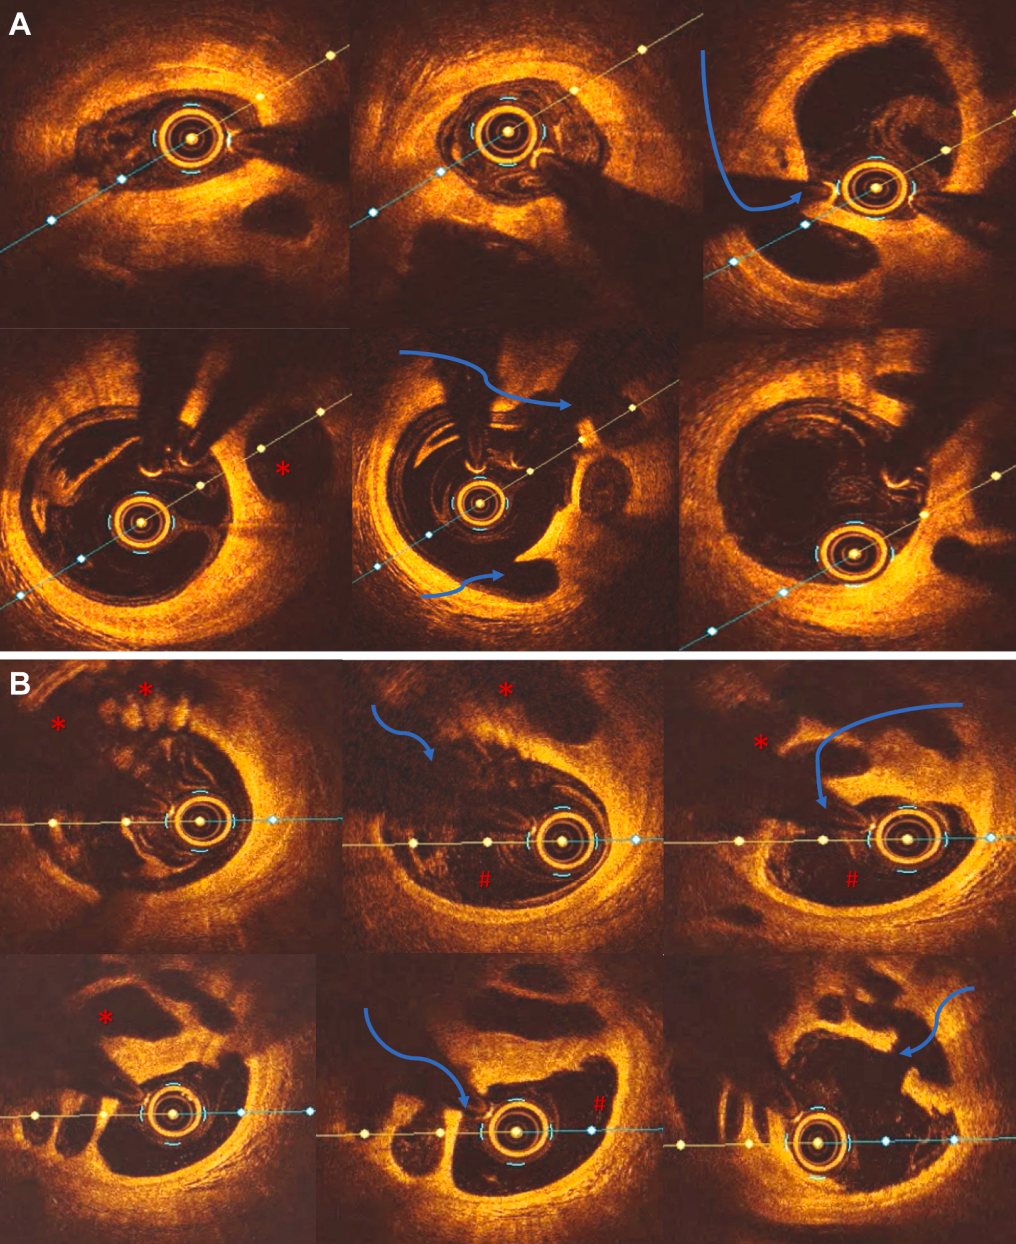

图5 病例2:右冠状动脉(RCA)支架植入前 OCT 图像

(A)纵向模式OC显示血栓复杂的通道化特征。(B-G)放大 OCT清晰显示血栓内的通道(∗),以及其后方完整的内弹力膜(红色箭头)和中膜(空心箭头),确认了病变的腔内性质而非血管壁内的夹层。第二个管腔后方完整的内弹力膜轨迹证实它位于血管腔内,提示为血栓而非自发性冠状动脉夹层(SCAD);血栓的边缘(#)可以追溯到由于血栓再通形成的次级管腔(@)(不要与 SCAD 的假腔混淆)。

后续的OCT检查揭示了真相(图5):在一个机化的管腔内结构中,存在多个细小不规则通道,符合血栓再通的特征,而无任何SCAD迹象。这促使我们启动了抗血栓治疗并进行了PCI。该病例凸显了造影误诊的风险以及OCT在实现诊断精确性方面的关键作用。